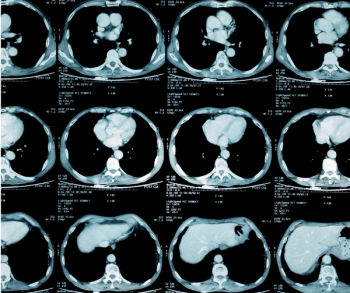

In a recent video interview, two radiology professors from the Yale School of Medicine discussed the impact of the iodinated contrast media (ICM) shortage and potential strategies, ranging from ICM dose reduction to possible deferment of non-urgent imaging, that may provide a viable path moving forward.